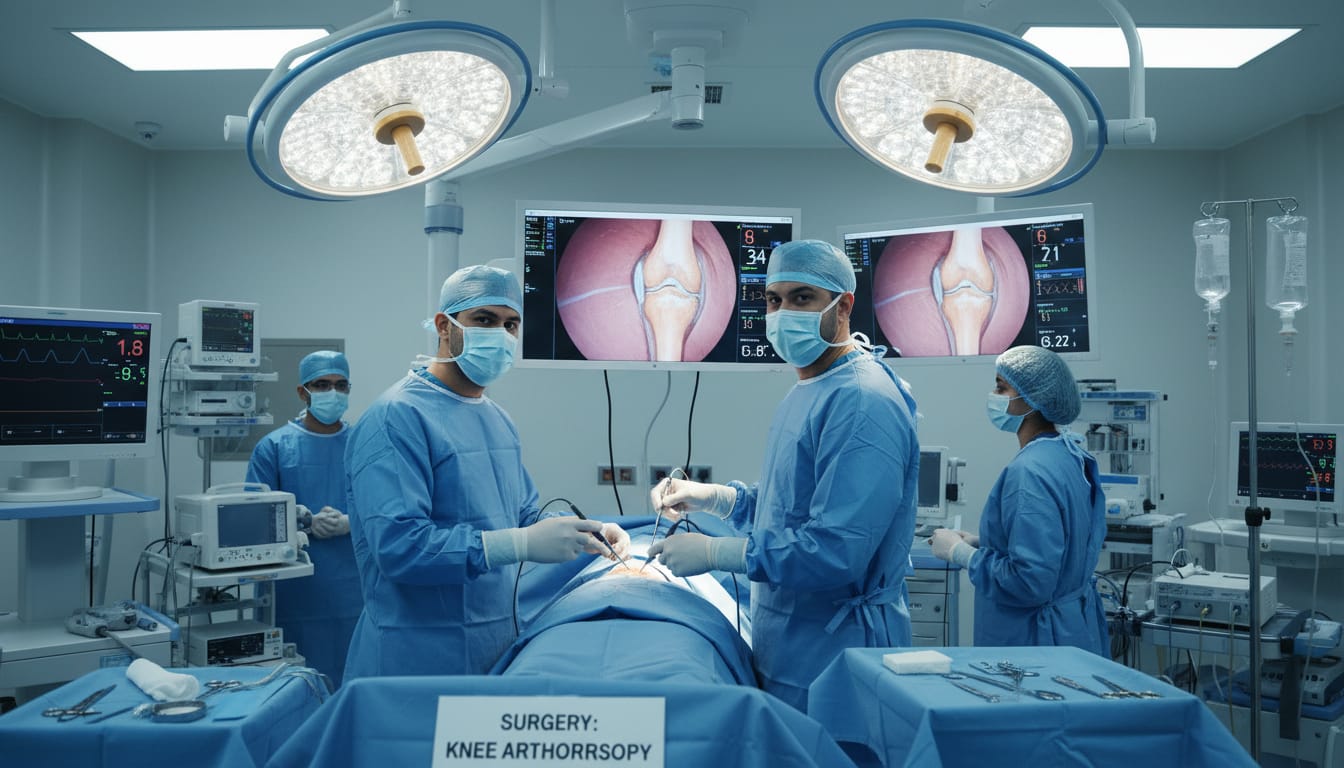

From joint replacement and arthroscopy to fracture management and spine care, our team uses evidence-based protocols and advanced imaging to plan safe, effective treatment tailored to your mobility goals.

- Advanced Orthopedic Care

- Modern Medical Technology